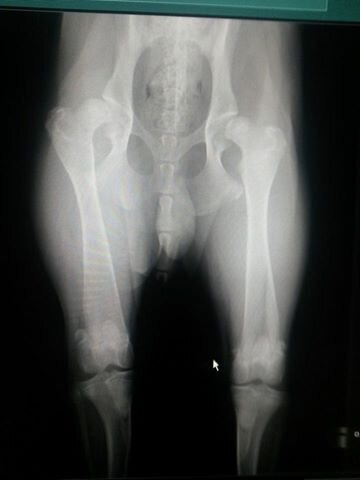

dit is een foto van zijn heupen.

Afbeelding

Ik heb het idee dat je hond scheef ligt op die foto. Welke da is deze foto gemaakt?

Joelle1996 schreef:

[ [url=m/x0CWy1.jpg]Afbeelding[/url] ]

Helaas is het duidelijk te zien op de foto. Mijn hond heeft na de diagnose nog 12 jaar pijnvrij mogen leven gelukkig. Hopelijk is dat bij jouw hond ook het geval :j